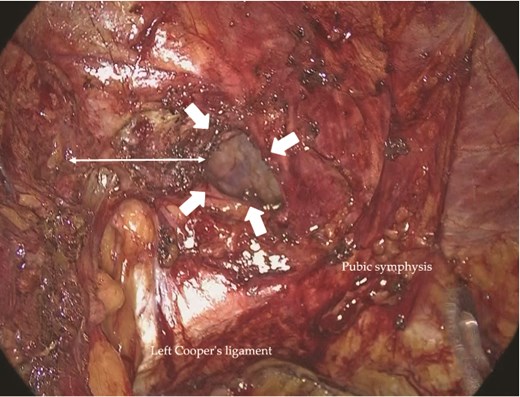

Under general anesthesia, a 12-mm camera port was inserted through the umbilicus, and two 5-mm ports were placed in the lower quadrants. Laparoscopic exploration revealed two mesh plugs on the left with fibrotic scarring and adhesions, which obscured the exact hernia orifice (Fig. 2). An incidental right direct hernia (M3) was also identified intraoperatively. Because severe adhesions were anticipated on the left, the operation was initiated on the right. A high peritoneal incision was initiated medial to the right anterior superior iliac spine (Fig. 3). The pseudosac was dissected while preserving the retropubic fascia, and the preperitoneal dissection was extended across the midline into the left side (Fig. 4). Approaching from the contralateral side allowed progressive entry into the adhesion-laden region through an unscarred plane, improving visualization and minimizing peritoneal injury.

Intraoperative view of the right inguinal region before repair. A right indirect inguinal hernia with a defect measuring >30 mm was observed (arrows). A high peritoneal incision was made near the right anterior superior iliac spine.